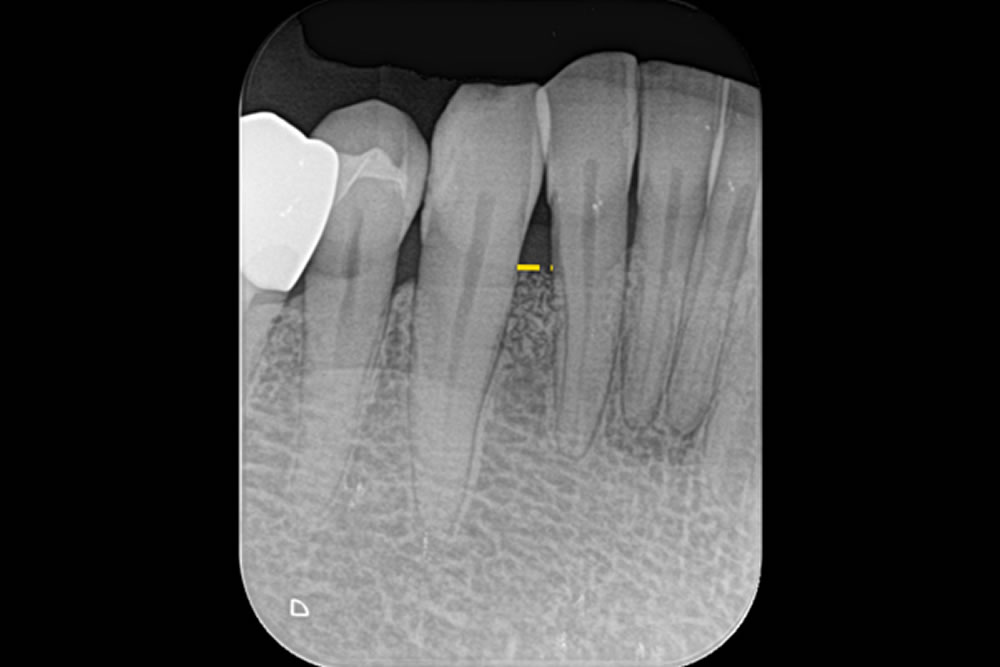

| 治療内容 | ・MIST(最小侵襲手術):できるだけ傷を小さくして回復を早める手術方法。 ・マイクロスコープ(顕微鏡)による精密歯周病治療。 ・Er:YAGレーザーで徹底的に清掃:歯根面から歯周病の原因となる「プラーク」を除去する治療。 |